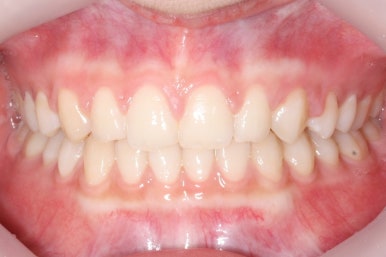

부산매복치아교정 상악 부분교정을 통해 매복치를 교정해준 이번 치료의 전후사진 비교입니다.

썩은 유치 대신 영구치 송곳니는 매우 자연스럽게 위치되었습니다. 아랫니는 교정하지 않았기 때문에 약간 삐뚠 느낌은 남아있지만 맞물림은 크게 문제가 없게 마무리 되었습니다.

얼굴 모습에서의 전후 비교입니다.

처음부터 매복치 이외에는 얼굴모습에서의 큰 문제가 없었고, 변화를 의도하지도 않았기 때문에 전후 모습의 큰 차이는 없습니다.

대신, 송곳니가 제위치되면서 웃거나 말할 때 미적으로 많이 개선된 것을 볼 수 있습니다.